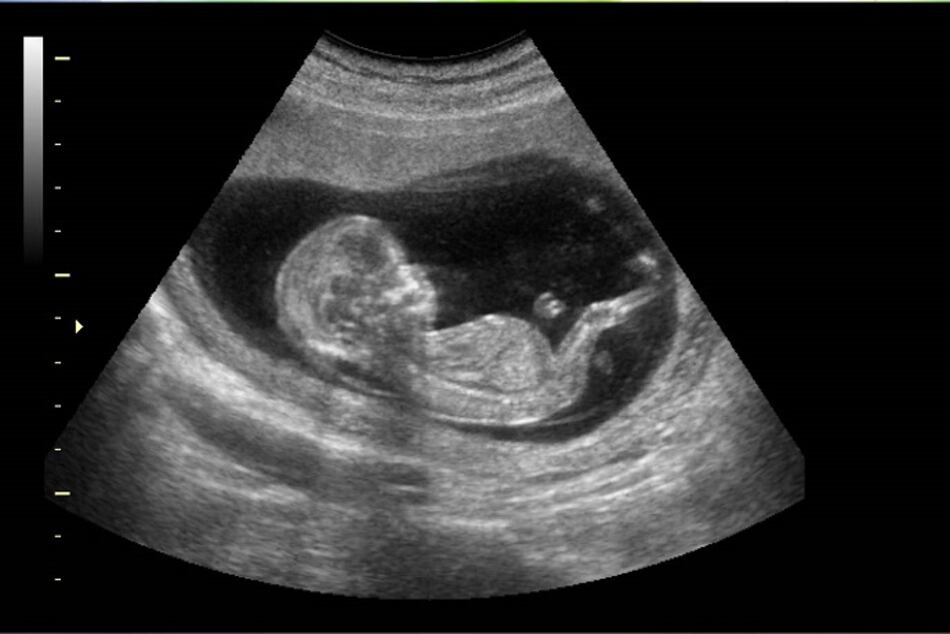

El riesgo de muerte fetal es aproximadamente el doble para las mujeres con Covid-19 en comparación con las que no lo tienen, y creció hasta cuadriplicarse durante el período en que la variante delta se volvió dominante, según un vasto estudio de una institución estatal de Estados Unidos difundido este viernes.

El análisis, realizado por los Centros para el Control y la Prevención de Enfermedades (CDC), se basó en más de 1.2 millones de partos ocurridos entre marzo de 2020 y septiembre de 2021 incluidos en una base de datos de hospitales.

En general, los casos de mortinatos fueron muy poco frecuentes, sumando 8,154, el 0.65% del total.

Pero el riesgo de muerte fetal era 1.90 veces más alto en las mujeres contagiadas con covid.

Concretamente, en ese periodo, 1.26% de los nacimientos fueron un mortinato entre las mujeres con covid, frente a 0.64% para el resto.

La variante delta incrementó ese riesgo, descubrieron los CDC, que analizaron los periodos antes y después de que esa variante se volvió dominante en el país, en julio de 2021.

Respecto a las no infectadas, el riesgo era 1.47 veces más alto entre las madres positivas para covid antes de la aparición de la variante delta y 4.04 veces más altos luego de que la variante se volvió dominante.